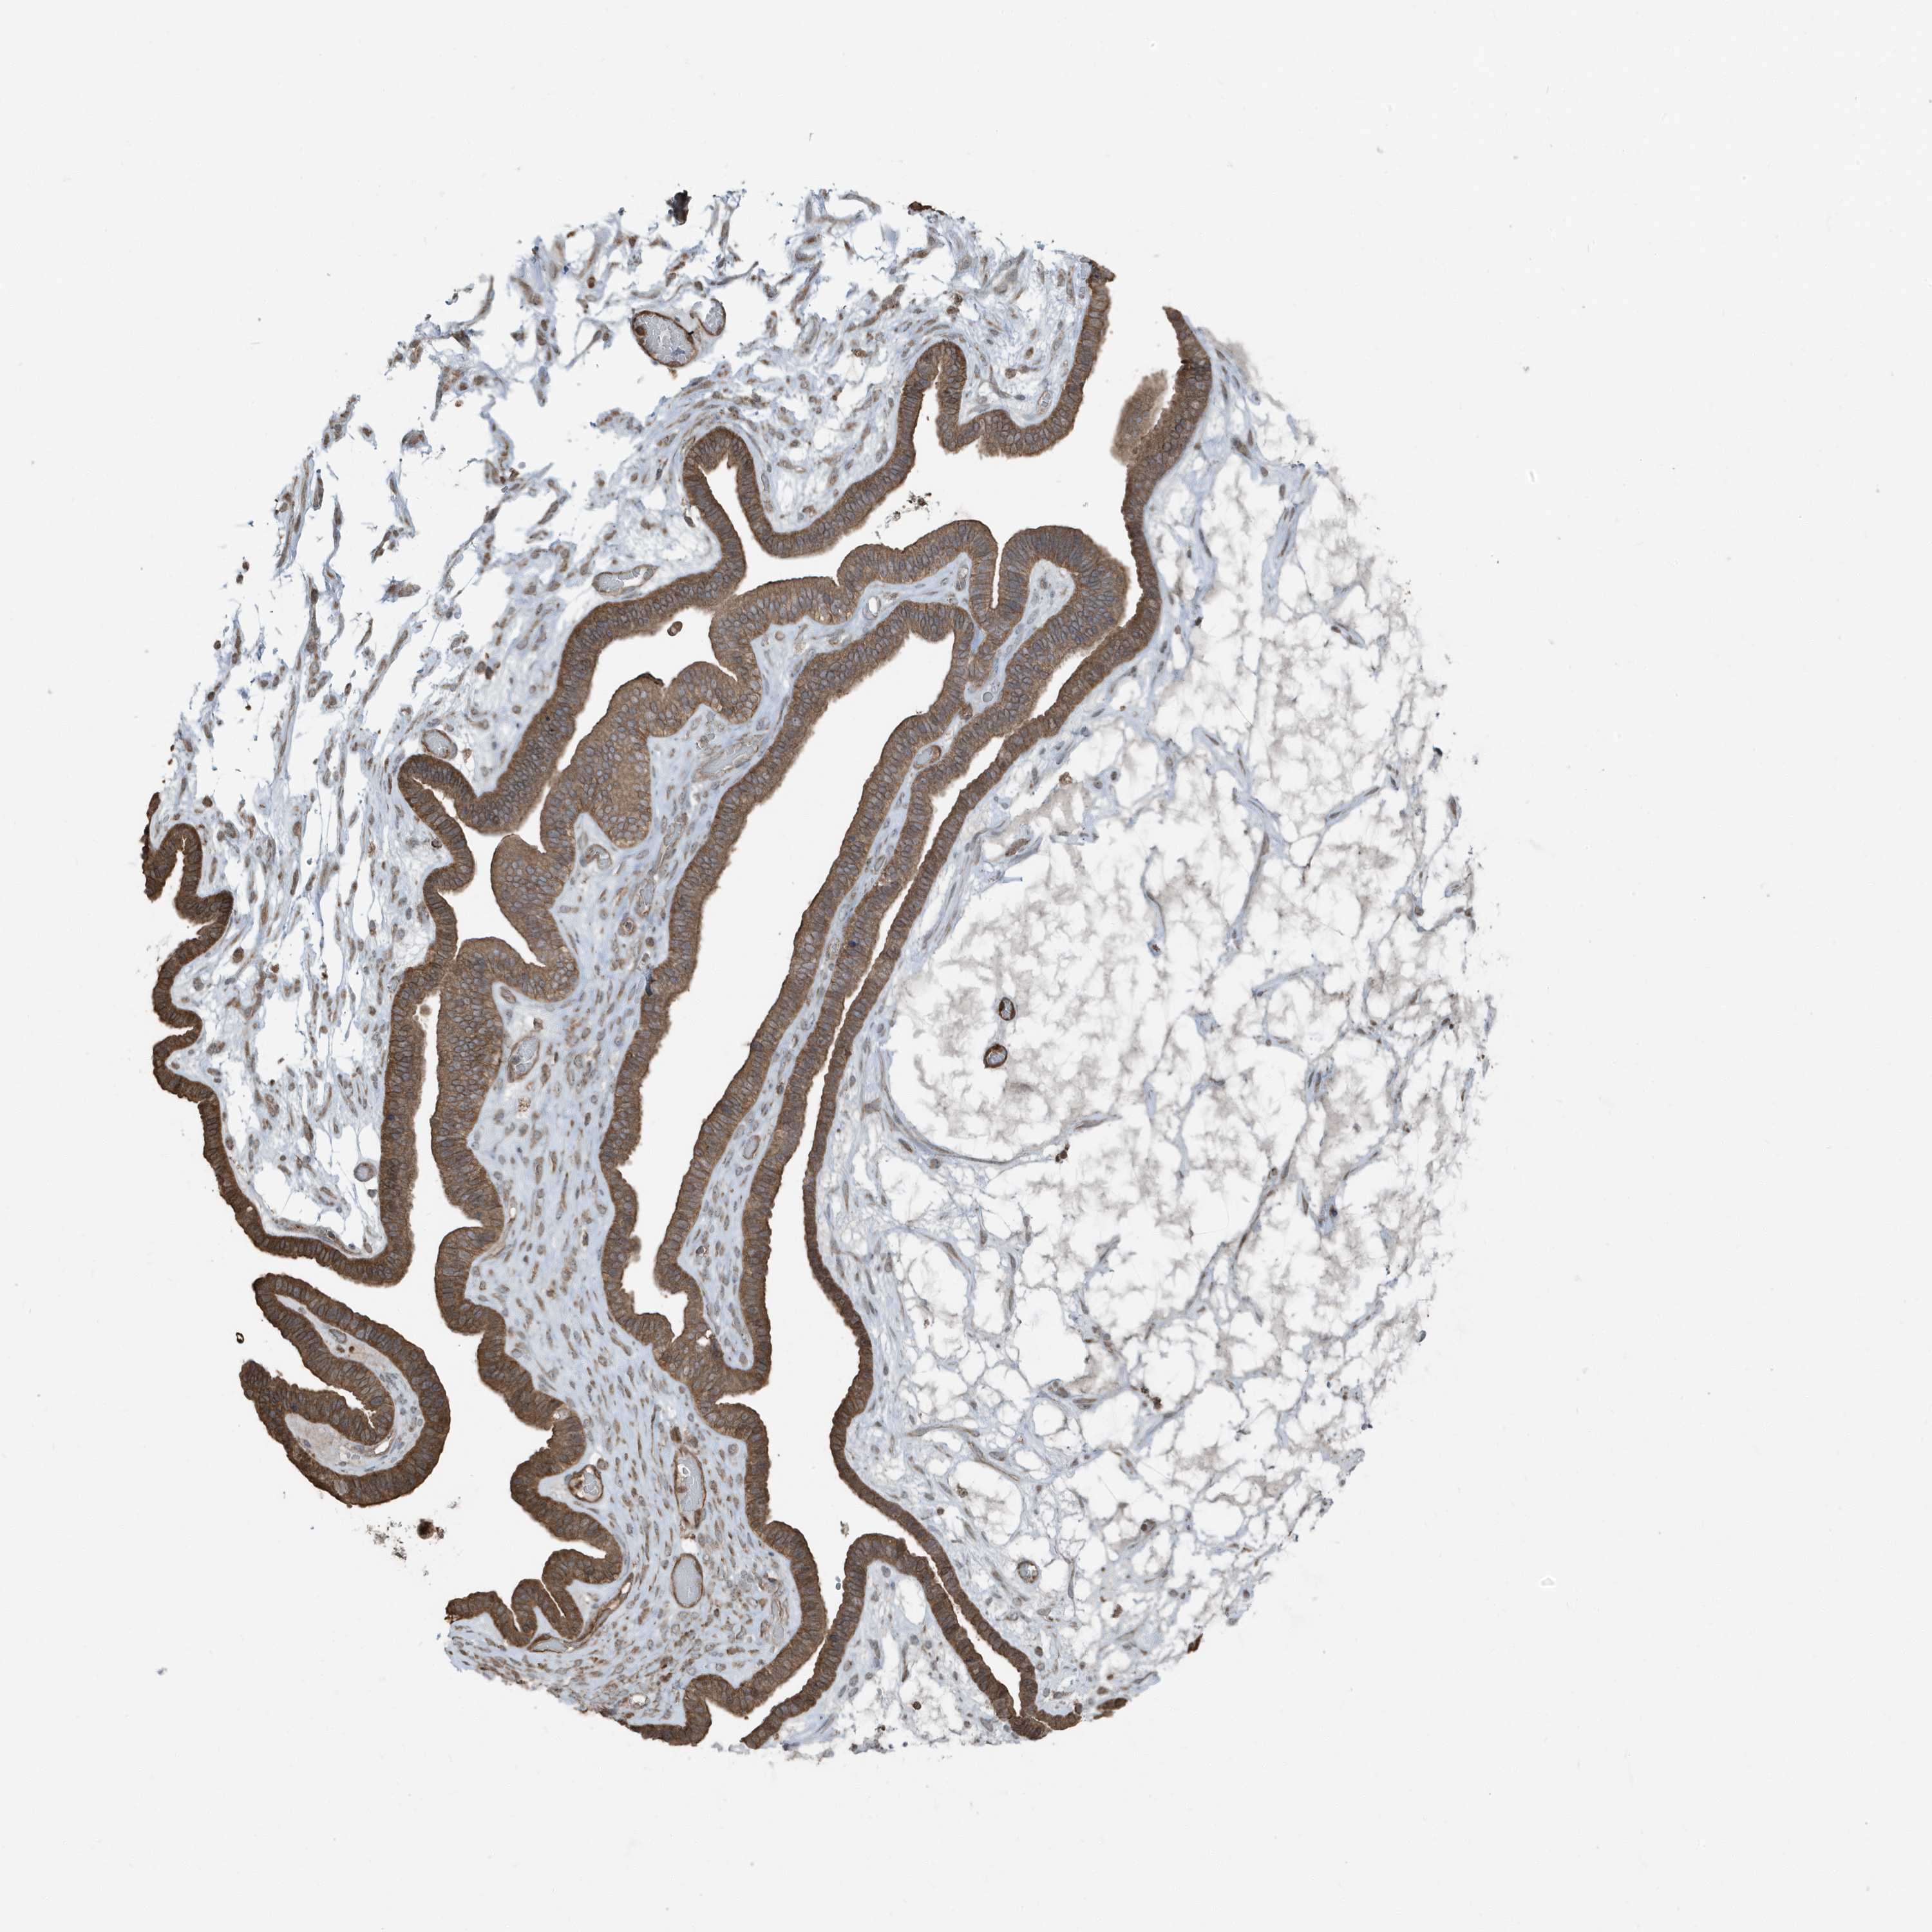

OVARIAN CANCER - Protein expressioni

A mouse-over function shows sample information and annotation data. Click on an image to view it in a full screen mode. Samples can be filtered based on level of antibody staining by selecting one or several of the following categories: high, medium, low and not detected. The assay and annotation is described here.

Note that samples used for immunohistochemistry by the Human Protein Atlas do not correspond to samples in the TCGA dataset.

Antibody stainingi

Antibody staining in the annotated cell types in the current human tissue is reported as not detected, low, medium, or high, based on conventional immunohistochemistry profiling in selected tissues. This score is based on the combination of the staining intensity and fraction of stained cells.

Each image is clickable and will lead to virtual microscopy that enables deeper exploration of all samples and also displays staining intensity scores, fraction scores and subcellular localization as well as patient and tissue information for each sample.

Antibody HPA035258

Staining

High

Medium

Low

Not detected

Intensity

Strong

Moderate

Weak

Negative

Quantity

>75%

75%-25%

<25%

None

Location

Nuclear

Cytoplasmic/membranous

Cytoplasmic/membranous,nuclear

Cystadenocarcinoma, serous, NOS

Carcinoma, endometroid

Cystadenocarcinoma, mucinous, NOS

Carcinoma, NOS